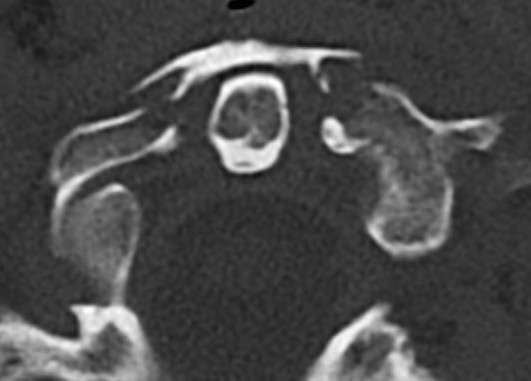

CT

Better defines displacement, ADI, LMD and bony avulsions of the transverse ligament

Avulsionlig avulsion

CT axial slices "Jefferson" (burst) fracture with bony avulsion (blue) of the transverse ligament